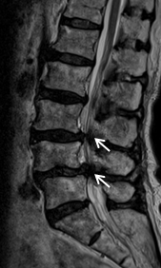

第2腰椎と第3腰椎に高度の骨粗鬆性椎体骨折を認めます。連鎖した骨折椎体は原型を失い扁平化・楔状化を来し、強い腰曲がり・脊柱後弯を呈しています。強い腰痛と体幹バランス不良のため歩行不能でした。MRIでは神経が強く圧迫されているのが分かります。

圧潰して原型を失った第2腰椎と第3腰椎に対して前方進入椎体置換術を行い、後方から広範囲矯正固定術を行っています。亀背は残りましたが、腰痛・神経症状は大幅に改善して杖で歩くことができるようになりました。